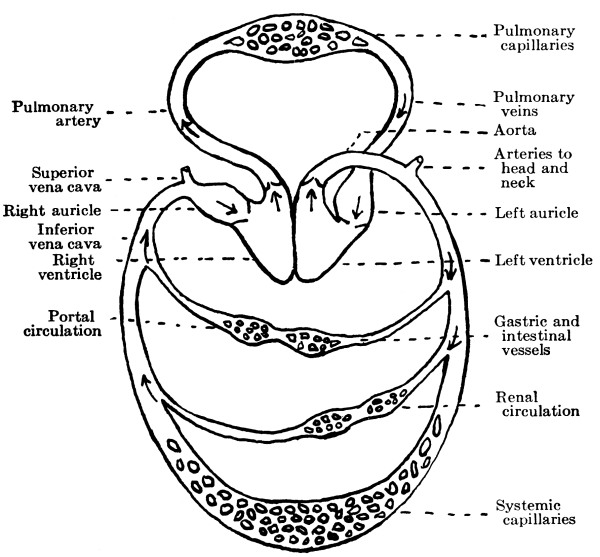

The Heart, 101—The Pericardium, 101—Cavities of the Heart, 103—The Endocardium, 103—The Valves of the Heart, 103—Circulation, 105—Circulation in the Fetus, 106—Arteries, 107—Veins, 109—Portal Circulation, 109—Pulmonary Circulation, 110—Nerves of the Heart, 110—Heart Sounds, 111—The Heart Beat, 111—Factors Affecting Circulation, 112—The Pulse, 113—Blood Pressure, 114—Nerve Supply of the Blood-vessels, 115—The Blood, 116—Composition of the Blood, 116—Coagulability of the Blood, 117—Blood-corpuscles, 118. |